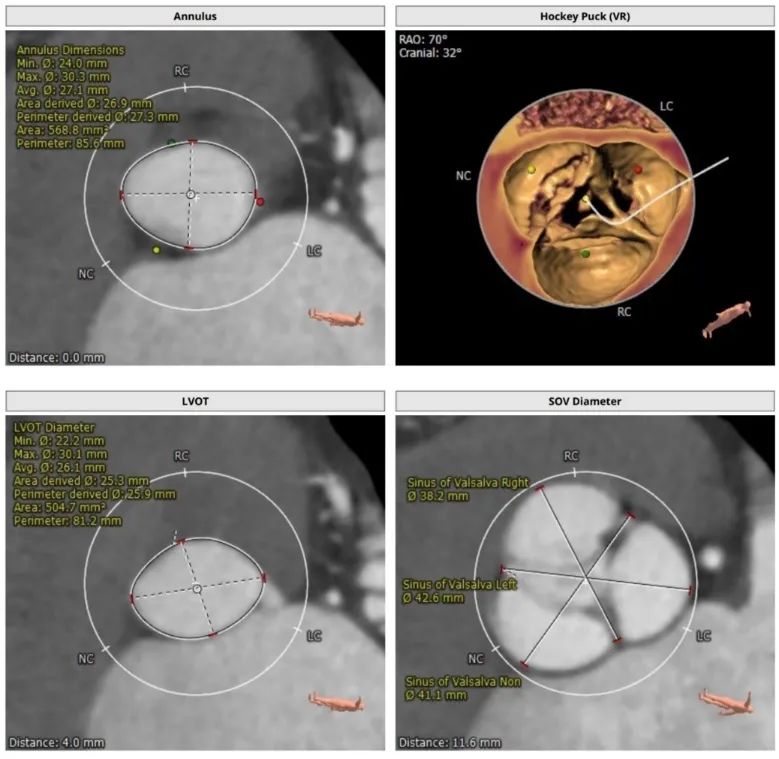

CT评估:三叶式主动脉瓣,瓣叶轻度增厚,无钙化,瓣环85.6mm,窦直径38~42mm。

主动脉瓣根部解剖